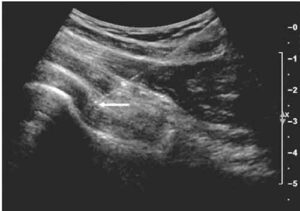

Un nuovo dispositivo a ultrasuoni potrebbe agevolare l’identificazione del rischio di rottura della placca arteriosa che causa infarto o ictus....